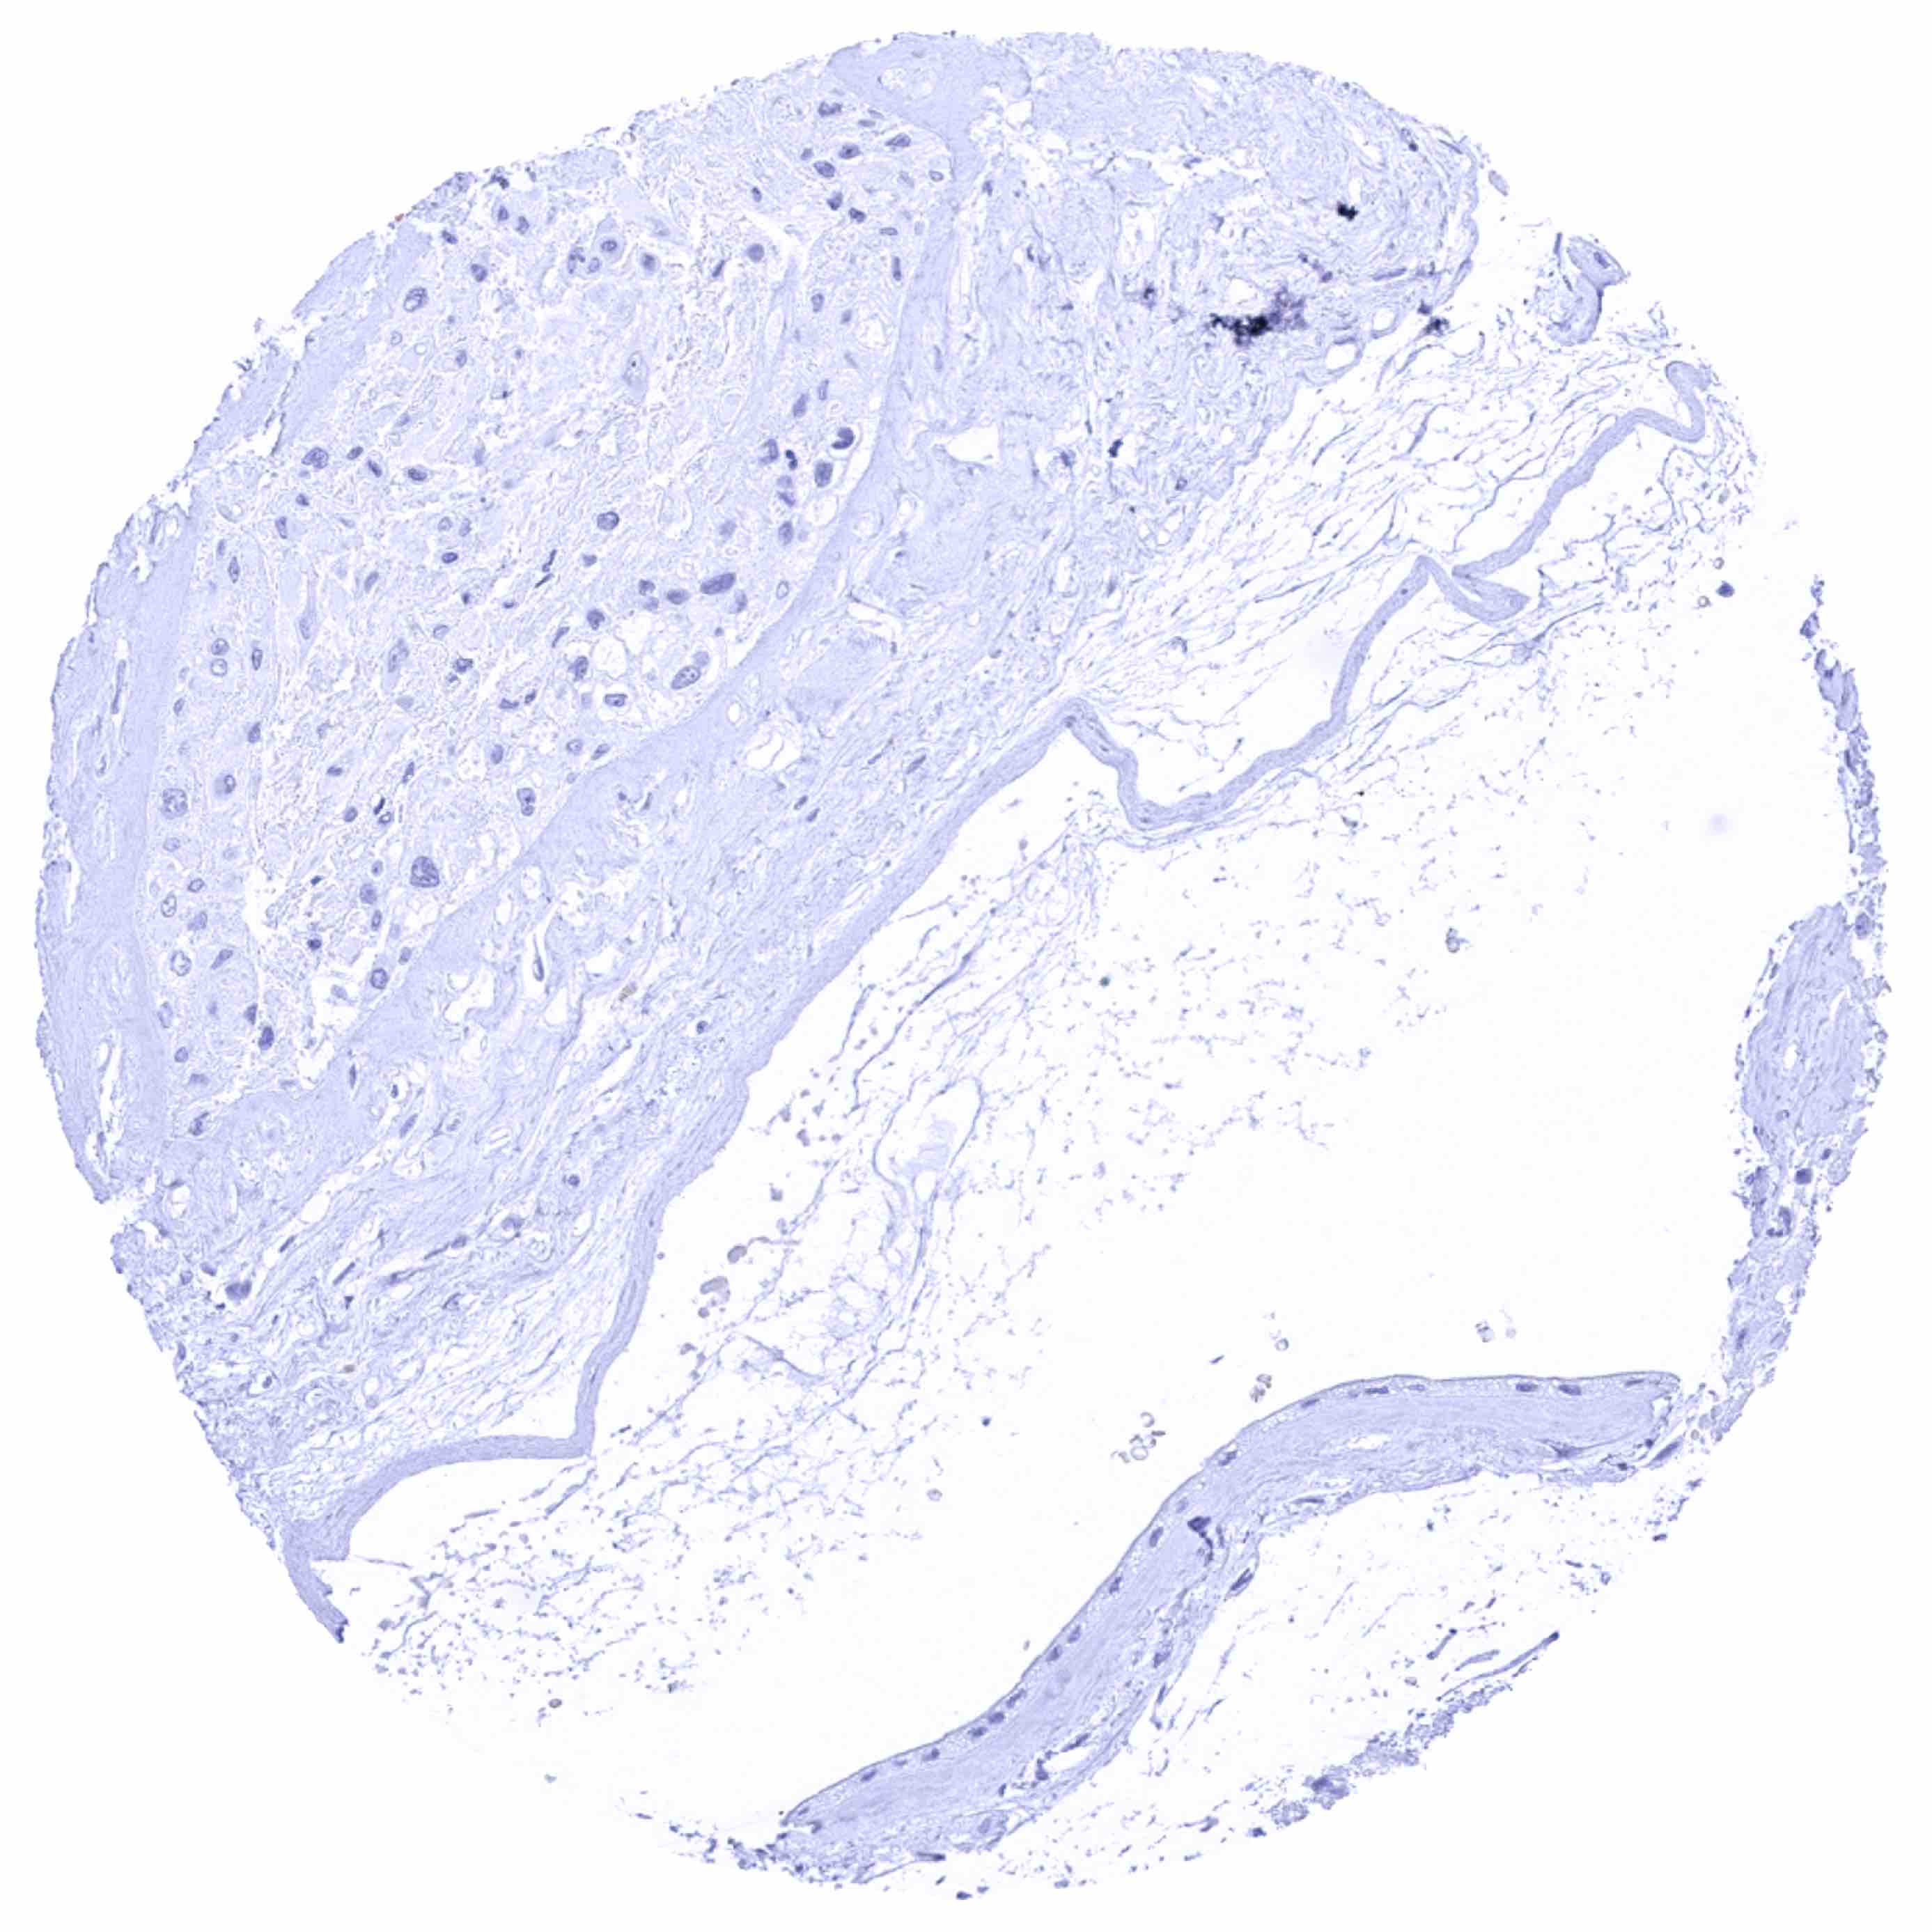

Esophagus, squamous epithelium